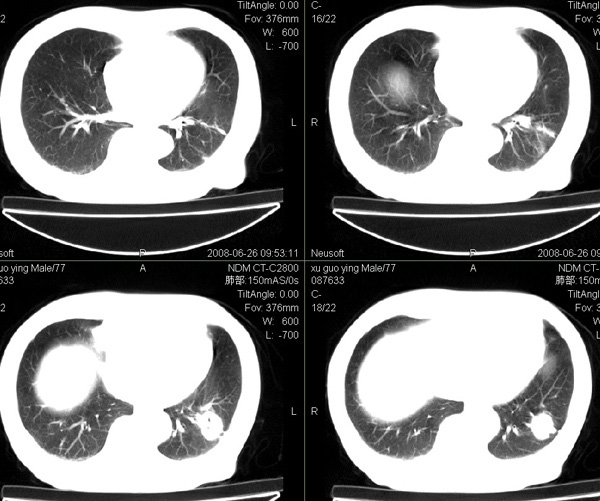

以下是引用狙击手在2008-6-26 20:16:00的发言:[br]上腹部除了胆囊大一点,其余未见明显异常,肺尖部见纤维条索样影,左肺下叶见空洞样占位,壁较厚,临近胸膜见牵拉,周围未见卫星灶,考虑:1:左下肺周围性肺癌;2:肺尖部陈旧性结合灶。

以下是引用liuqiang在2008-6-26 21:11:00的发言:[br]上腹部除了胆囊大一点,其余未见明显异常,肺尖部见纤维条索样影,左肺下叶见空洞样占位,壁较厚,临近胸膜见牵拉,周围未见卫星灶,考虑:1:左下肺周围性肺癌;2:肺尖部陈旧性j结核灶。